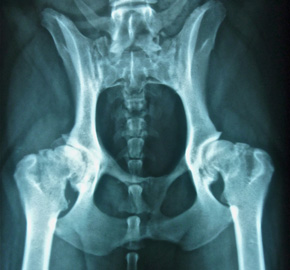

• Röntgen mit modernster digitaler Röntgenanlage

Offizielle HD, ED, und Rückenröntgen, Kontraströntgen

Schwierige Fälle werden seit 20 Jahren zusammen mit dem Röntgenspezialisten Prof. Mark Flückiger ausgewertet